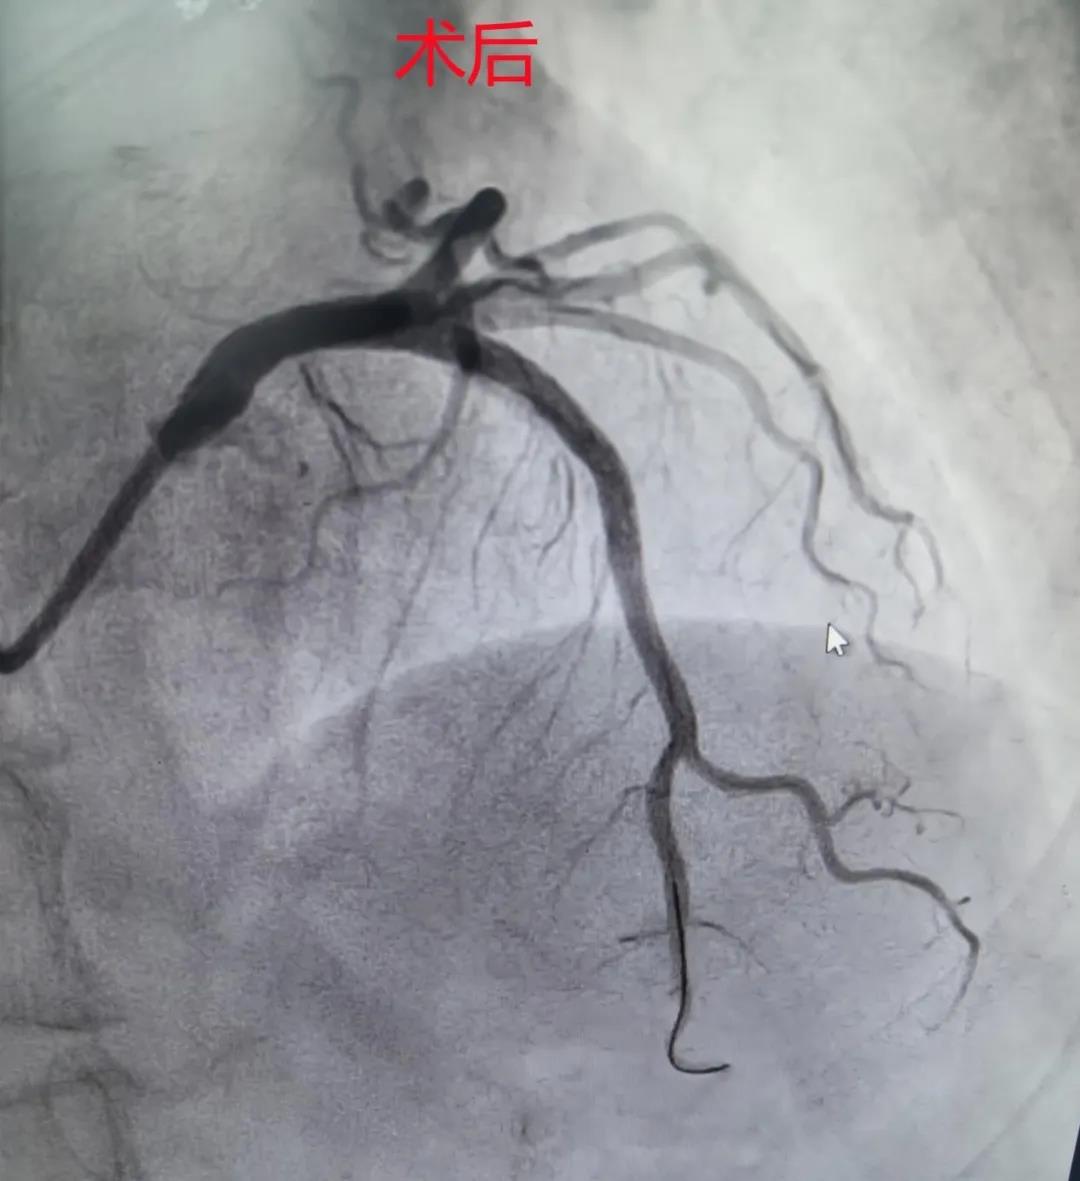

旋磨成功后,再次通过IVUS复查评估,确认钙化环被有效打磨、断裂,随后顺利在病变处植入药物洗脱支架一枚,术后再次IVUS评估显示,支架贴壁良好、膨胀完全,管腔面积达到理想标准(最小管腔面积达8.52mm²),最终造影显示,前降支血流恢复通畅(TIMI 3级)。

此次手术的成功,体现了我院心血管内科介入团队在精准介入诊疗方面的专业能力,标志着我院在复杂、高危、疑难冠脉介入治疗领域取得了新的突破。